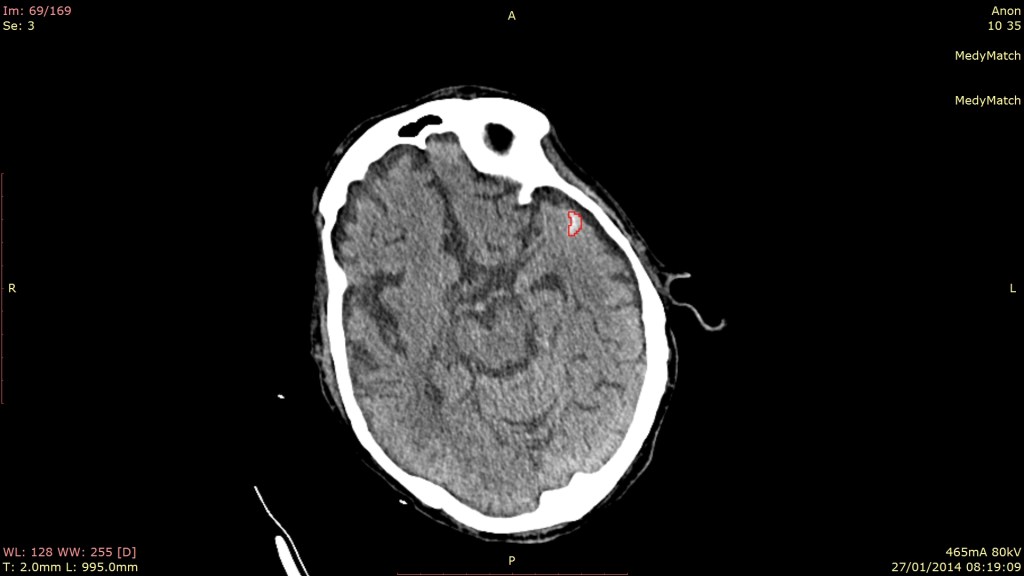

MedyMatch Technology bills itself as an artificial intelligence healthcare startup. It’s applying AI in the form of “deep vision and advanced cognitive analytics” to the analysis of medical imaging scans to help radiologists or emergency department physicians recognise hard to spot abnormalities and in turn make better decisions.

As it stands today, MedyMatch is applying its tech to the area of stroke diagnosis, ensuring that stroke victims are given the correct treatment. That’s because, I’m told, there are generally two major types of stroke, each requiring very different treatment. When that treatment is applied incorrectly, not only can it be life threatening but also the difference between returning to a relatively normal life or needing further and costly care indefinitely.

One type of stroke is where someone’s blood vessel bursts in the brain and that person begins to bleed, while the other type is a clot in a blood vessel, where the blood stops flowing to that part of the brain. In the case of a blood clot, the doctor would prescribe a clot busting drug which would open up the blood vessels to get the blood flowing again. However, if the stoke has resulted from a burst vessel and the doctor accidentally prescribes the clot busting drug, it will increase the flow of the bleed, causing severe damage.

“MedyMatch compares billions of data points in images to give the physician in the emergency room an augmented set of eyes on the medical imaging they are looking at and can easily help the doctor pinpoint the location of the bleed and how bad it is. It is essentially a second look and a second opinion to support or refute the doctor’s initial diagnosis.”